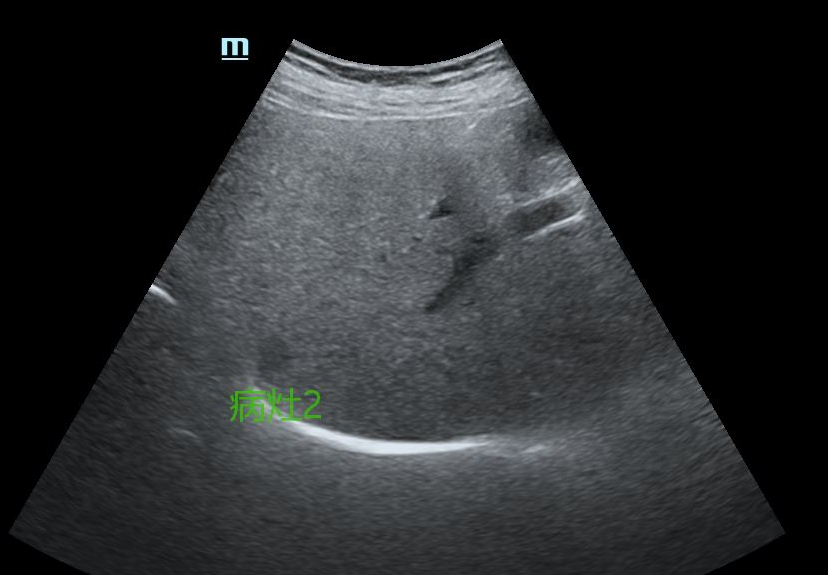

结肠癌肝转移患者多发转移病灶